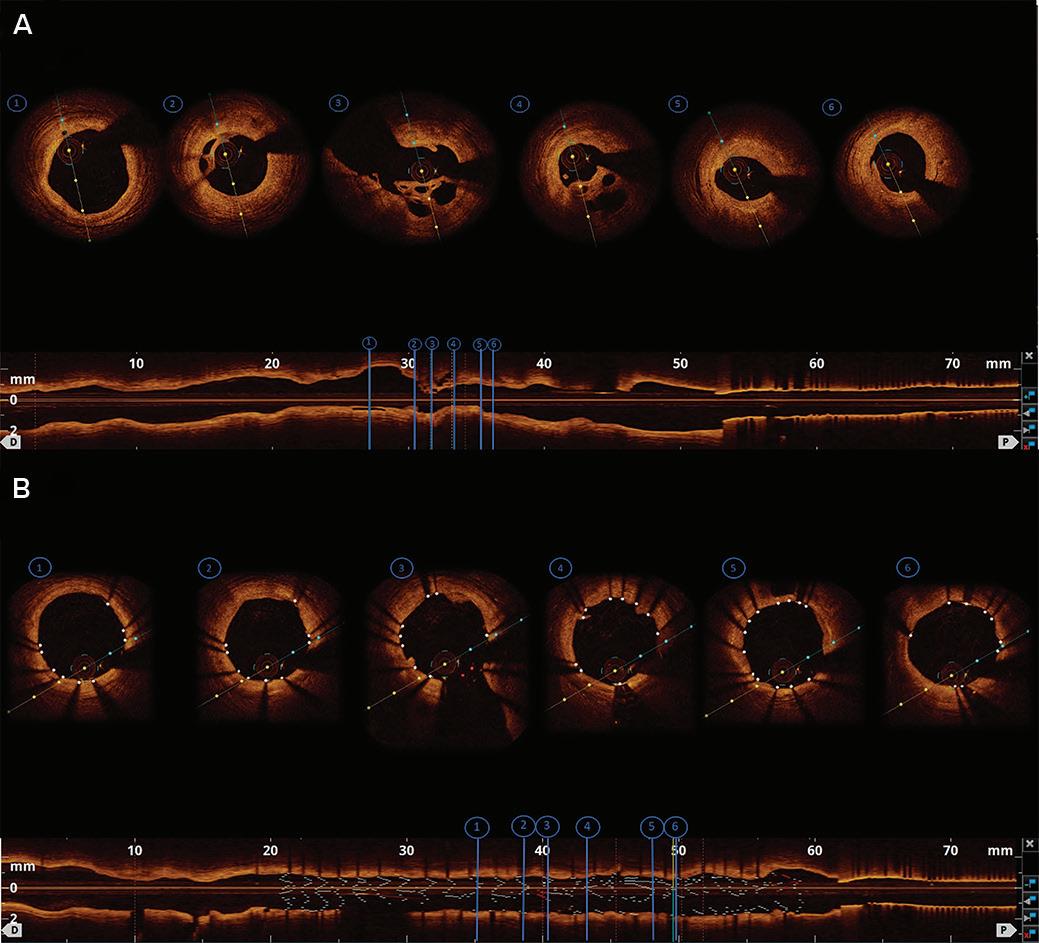

Hs-cTnT 12–52 ng/l and delta 3 to <5 ng/l at 1–3 h

Hs-cTnT >sex-specific 99th percentile or high risk score and 2–3 h delta >RCV

Hs-cTnT <sex-specific 99th percentile and low risk score

Not applicable

0/1 and 0/3 h 0/1, 0/2 and 0/3 h 0/2 and 0/3 h

Recommends the use of HEART risk score

Recommends the use of GRACE risk score models for estimating prognosis

Requires the use of HEART score for final disposition

Hs-cTn used Hs-cTnT Hs-cTnT and TnI Hs-cTnT and TnI

AMI = acute MI; APSC = Asian Pacific Society of Cardiology; ED = emergency department; ESC = European Society of Cardiology; GRACE = Global Registry of Acute Coronary Events; HEART = History, Electrocardiogram, Age, Risk factors and Troponin; Hs-cTn = high-sensitivity cardiac troponin; Hs-cTnT = high-sensitivity cardiac troponin T; RCV = reference change value; Malaysian = Malaysian Expert Consensus Group; TnI = Troponin I.